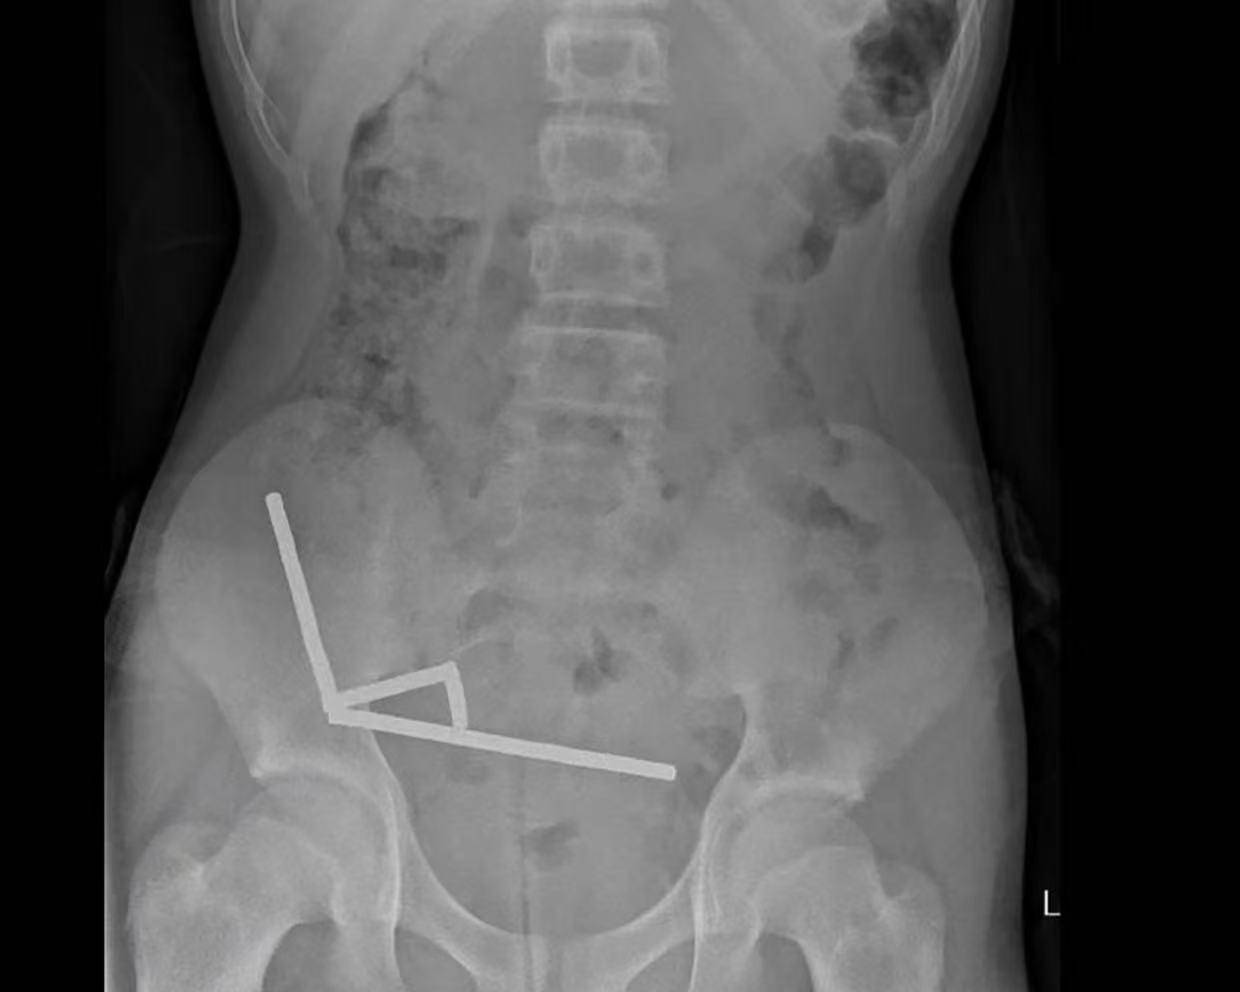

据悉,这名未透露姓名的少年在持续腹痛4天后被送往新西兰北岛的一家医院皇冠信用網出租代理 。医生通过X光检查发现,这些磁铁在他的肠道内互相吸附,形成了四条链状结构。

▲X光显示皇冠信用網出租代理 ,磁铁在男孩体内紧密吸附成链状结构

医生介绍,男孩大约一周前吞下了80至100颗大功率钕磁铁,每颗尺寸为5×2毫米皇冠信用網出租代理 。报告称,这些磁铁通过一家跨境电商平台购买。